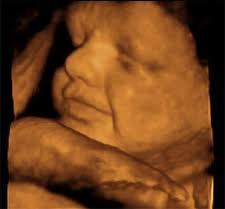

Feto cara cara2 Feto Oreja manos carita bebe Barret Barrett1 Pólipo Diverticulos Cancer rectal Transverso Duodeno Rayos%20x.jpg